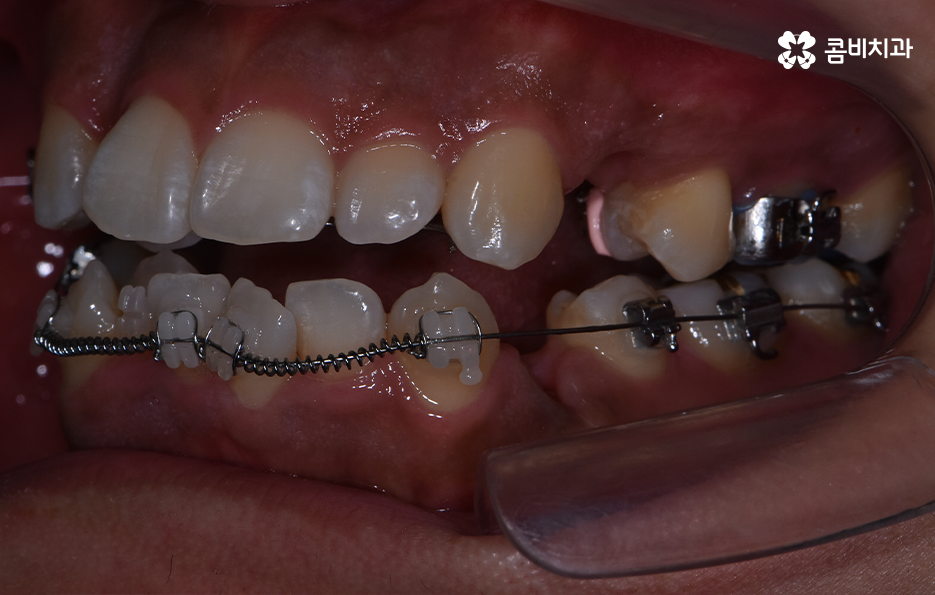

치아교정을 위한 발치교정 과정은 대부분 소구치 라고 불리는 첫번째 작은 어금니를 발치하게 되며 좌우, 위 아래 총 4개의 소구치를 발치한 후에 덧니가 재배열 될 수 있는 공간을 만들기 위하여 우선 송곳니를 후방으로 이동시키고 있어요

그 다음으로는 송곳니가 후방으로 이동하면서 확보된 공간으로 앞니의 배열을 가지런하게 맞추고 있는데요. 앞니의 재배열과 함께 발치 교정으로 인해 빈 공간이 발생한 부분을 없애고 전체적인 치열을 미세하게 조절하게 되는데 발치교정은 치아의 움직임이 많은 편이기 때문에 교합이 잘 맞도록 마무리 배열을 잘해야 하며 그와 함께 치아가 많이 움직이는 만큼 얼굴형의 변화와 입술라인 등의 변화가 클 수 있다는 점에서 치료 후 결과를 잘 예측하여 처음 치료 계획부터 마무리까지 섬세하게 진행하실 필요가 있어요